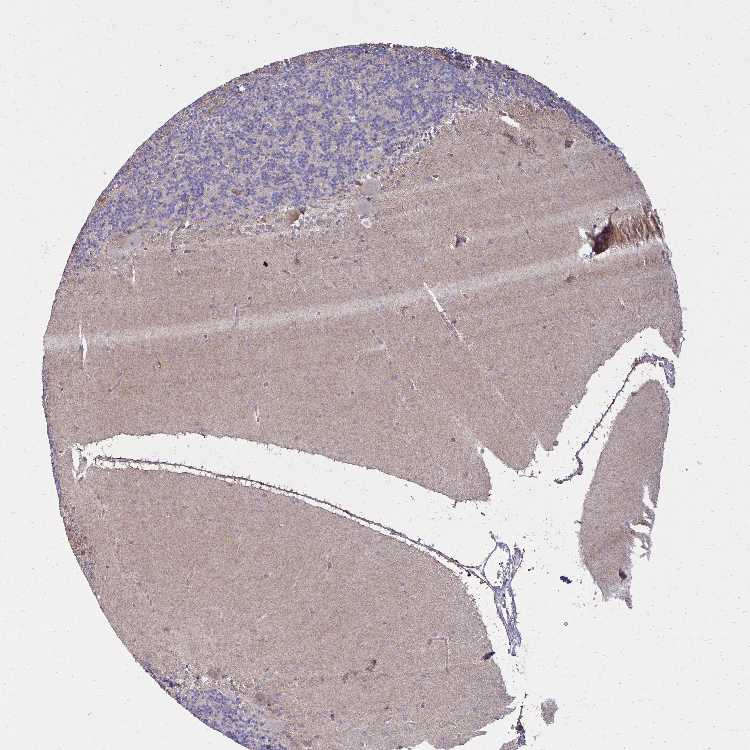

CEREBELLUM - Antibody stainingi

Antibody staining in the annotated cell types in the current human tissue is reported as not detected, low, medium, or high, based on conventional immunohistochemistry profiling in selected tissues. This score is based on the combination of the staining intensity and fraction of stained cells.

Each image is clickable and will lead to virtual microscopy that enables deeper exploration of all samples and also displays staining intensity scores, fraction scores and subcellular localization as well as patient and tissue information for each sample.

Antibody HPA007162Antibody CAB035986Antibody CAB062546

Purkinje cells HighMediumNot detected

Cells in granular layer Not detectedNot detectedNot detected

Cells in molecular layer LowNot detectedNot detected